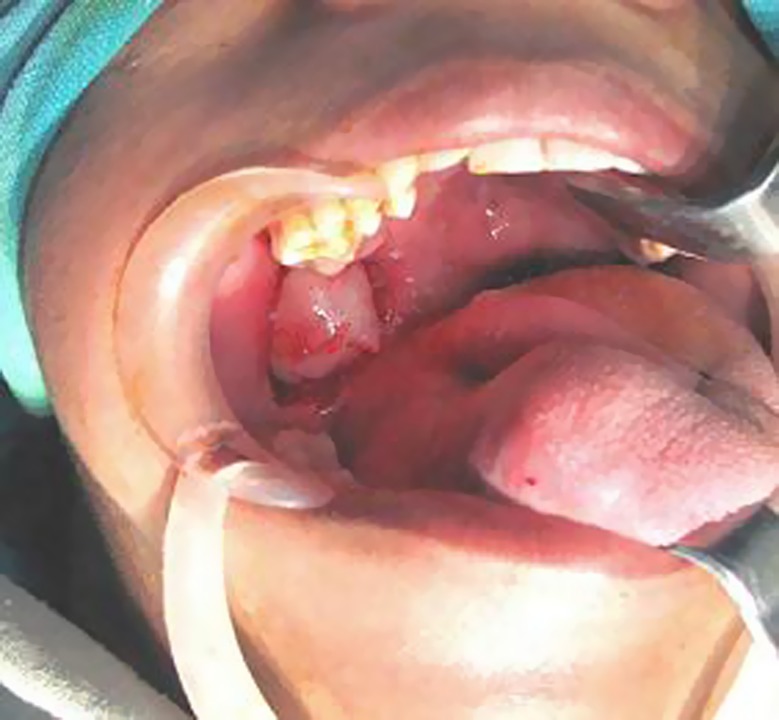

The complete blood count, biochemistry tests (aspartate aminotransferase, alanine aminotransferase, lactate dehydrogenase, alkaline phosphatase, total protein, and C-reactive protein), and renal function tests (uric acid, blood urea nitrogen, and creatinine) all gave results within normal limits. Fine needle aspiration cytology (FNAC) was performed, and the lesion was diagnosed as a benign tumor of neurogenic origin. Based on the diagnosis of a benign tumor, excision of the tumor was performed under general anesthesia. The excised tumor measured about 20 × 20 × 20 mm and was encapsulated with fibrous connective tissue. Macroscopic appearance was oval, solid, and grayish white in color (Fig. 3) and had diffuse brown pigmentation on the cut surface.

Fig. 3.

Intra operative picture shows exposed tumor mass